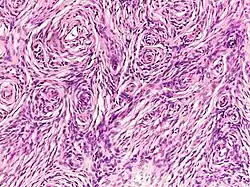

| Neurofibroma of the skin in a person with neurofibromatosis type I | |